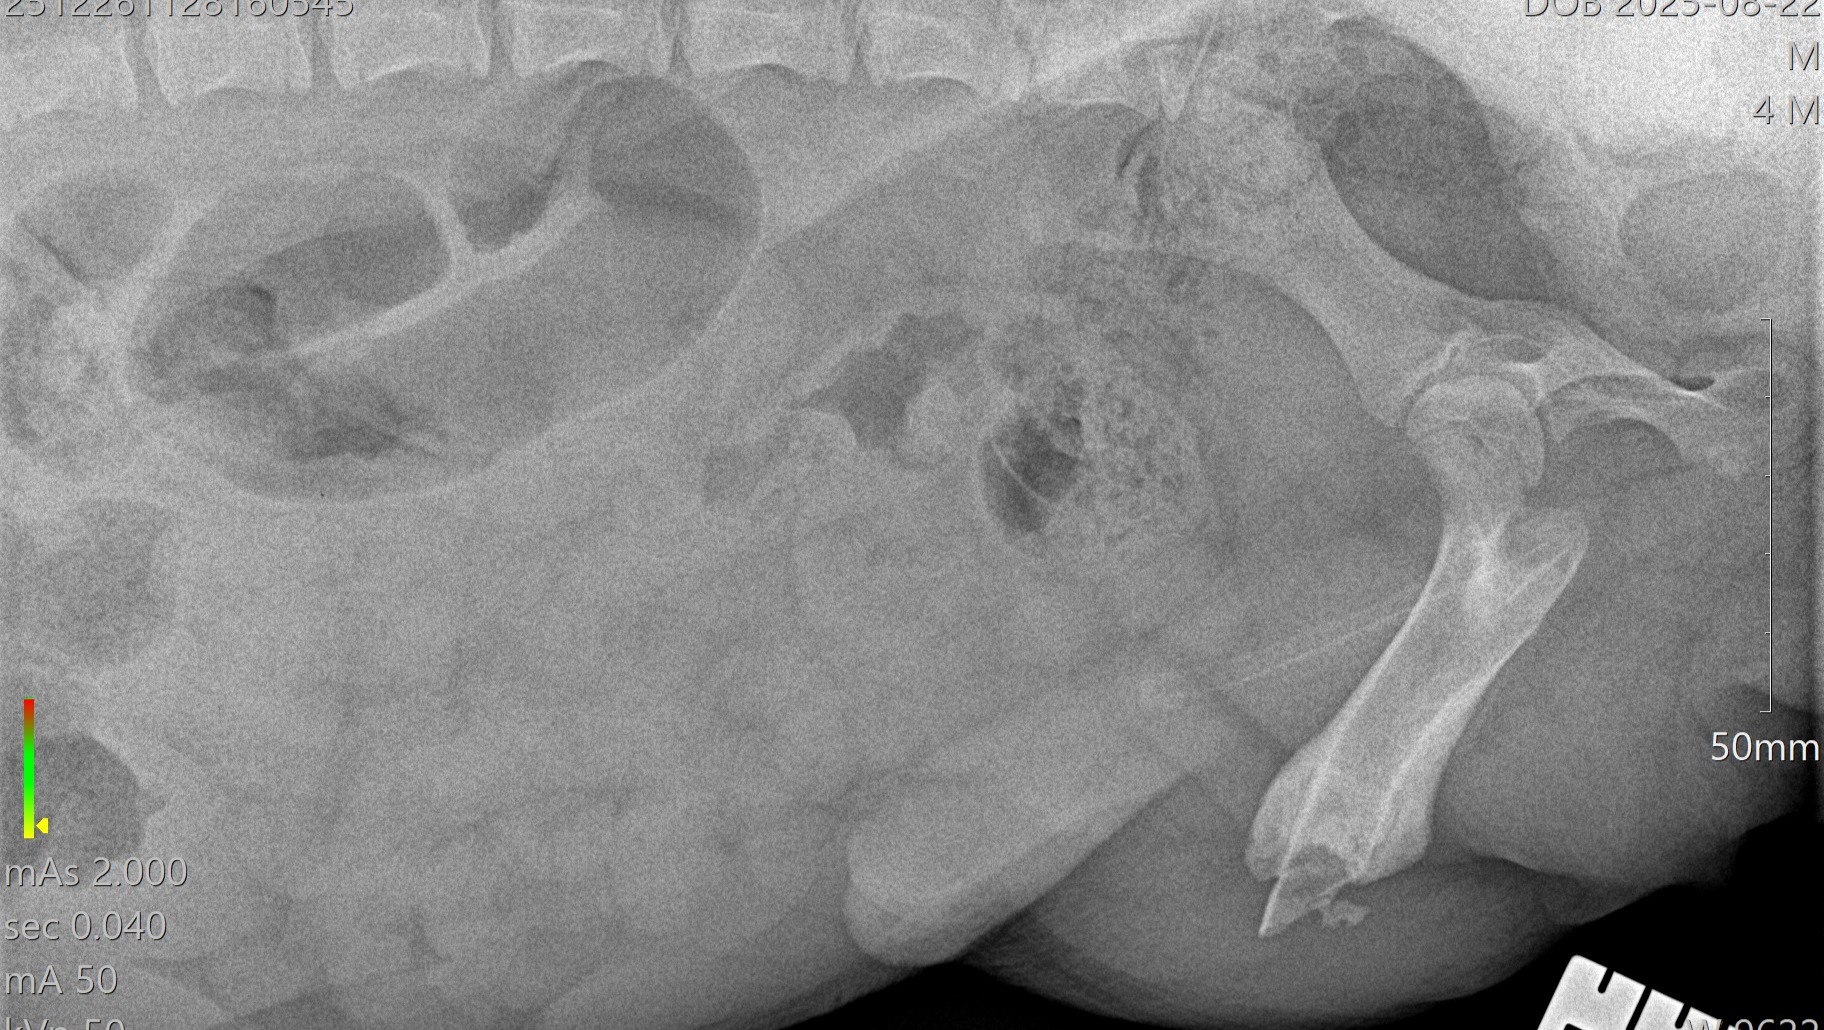

One year ago, we shared the story of a little dog in Puerto Rico who had nearly given up hope. Juanita was found lying on the side of the road in the blistering heat, unable to move after being hit by a car. She had multiple fractures in her pelvis and femur, and her tail was so badly damaged it required amputation. Someone had left a solo cup with water nearby, but she was too broken and weak to reach it. Cars drove past her for days, and when Ruby finally arrived to rescue her, she could barely lift her head. The look in her eyes said it all—she had been waiting for someone to finally care.

But Juanita’s story isn’t over yet. Earlier this year, Juanita needed another surgery on her leg to support her recovery and give her the best chance at a healthy future. She has been incredibly brave through every procedure, every setback, and every step forward. While she continues to improve, her medical costs have added up significantly once again. Between her additional surgery, ongoing care, training, and recovery, the expenses have exceeded what our small rescue can cover on our own.

First round of x-rays: $415

CSU Consult: $242

Second surgery procedure: $1,500

second radiographs and exams: $350